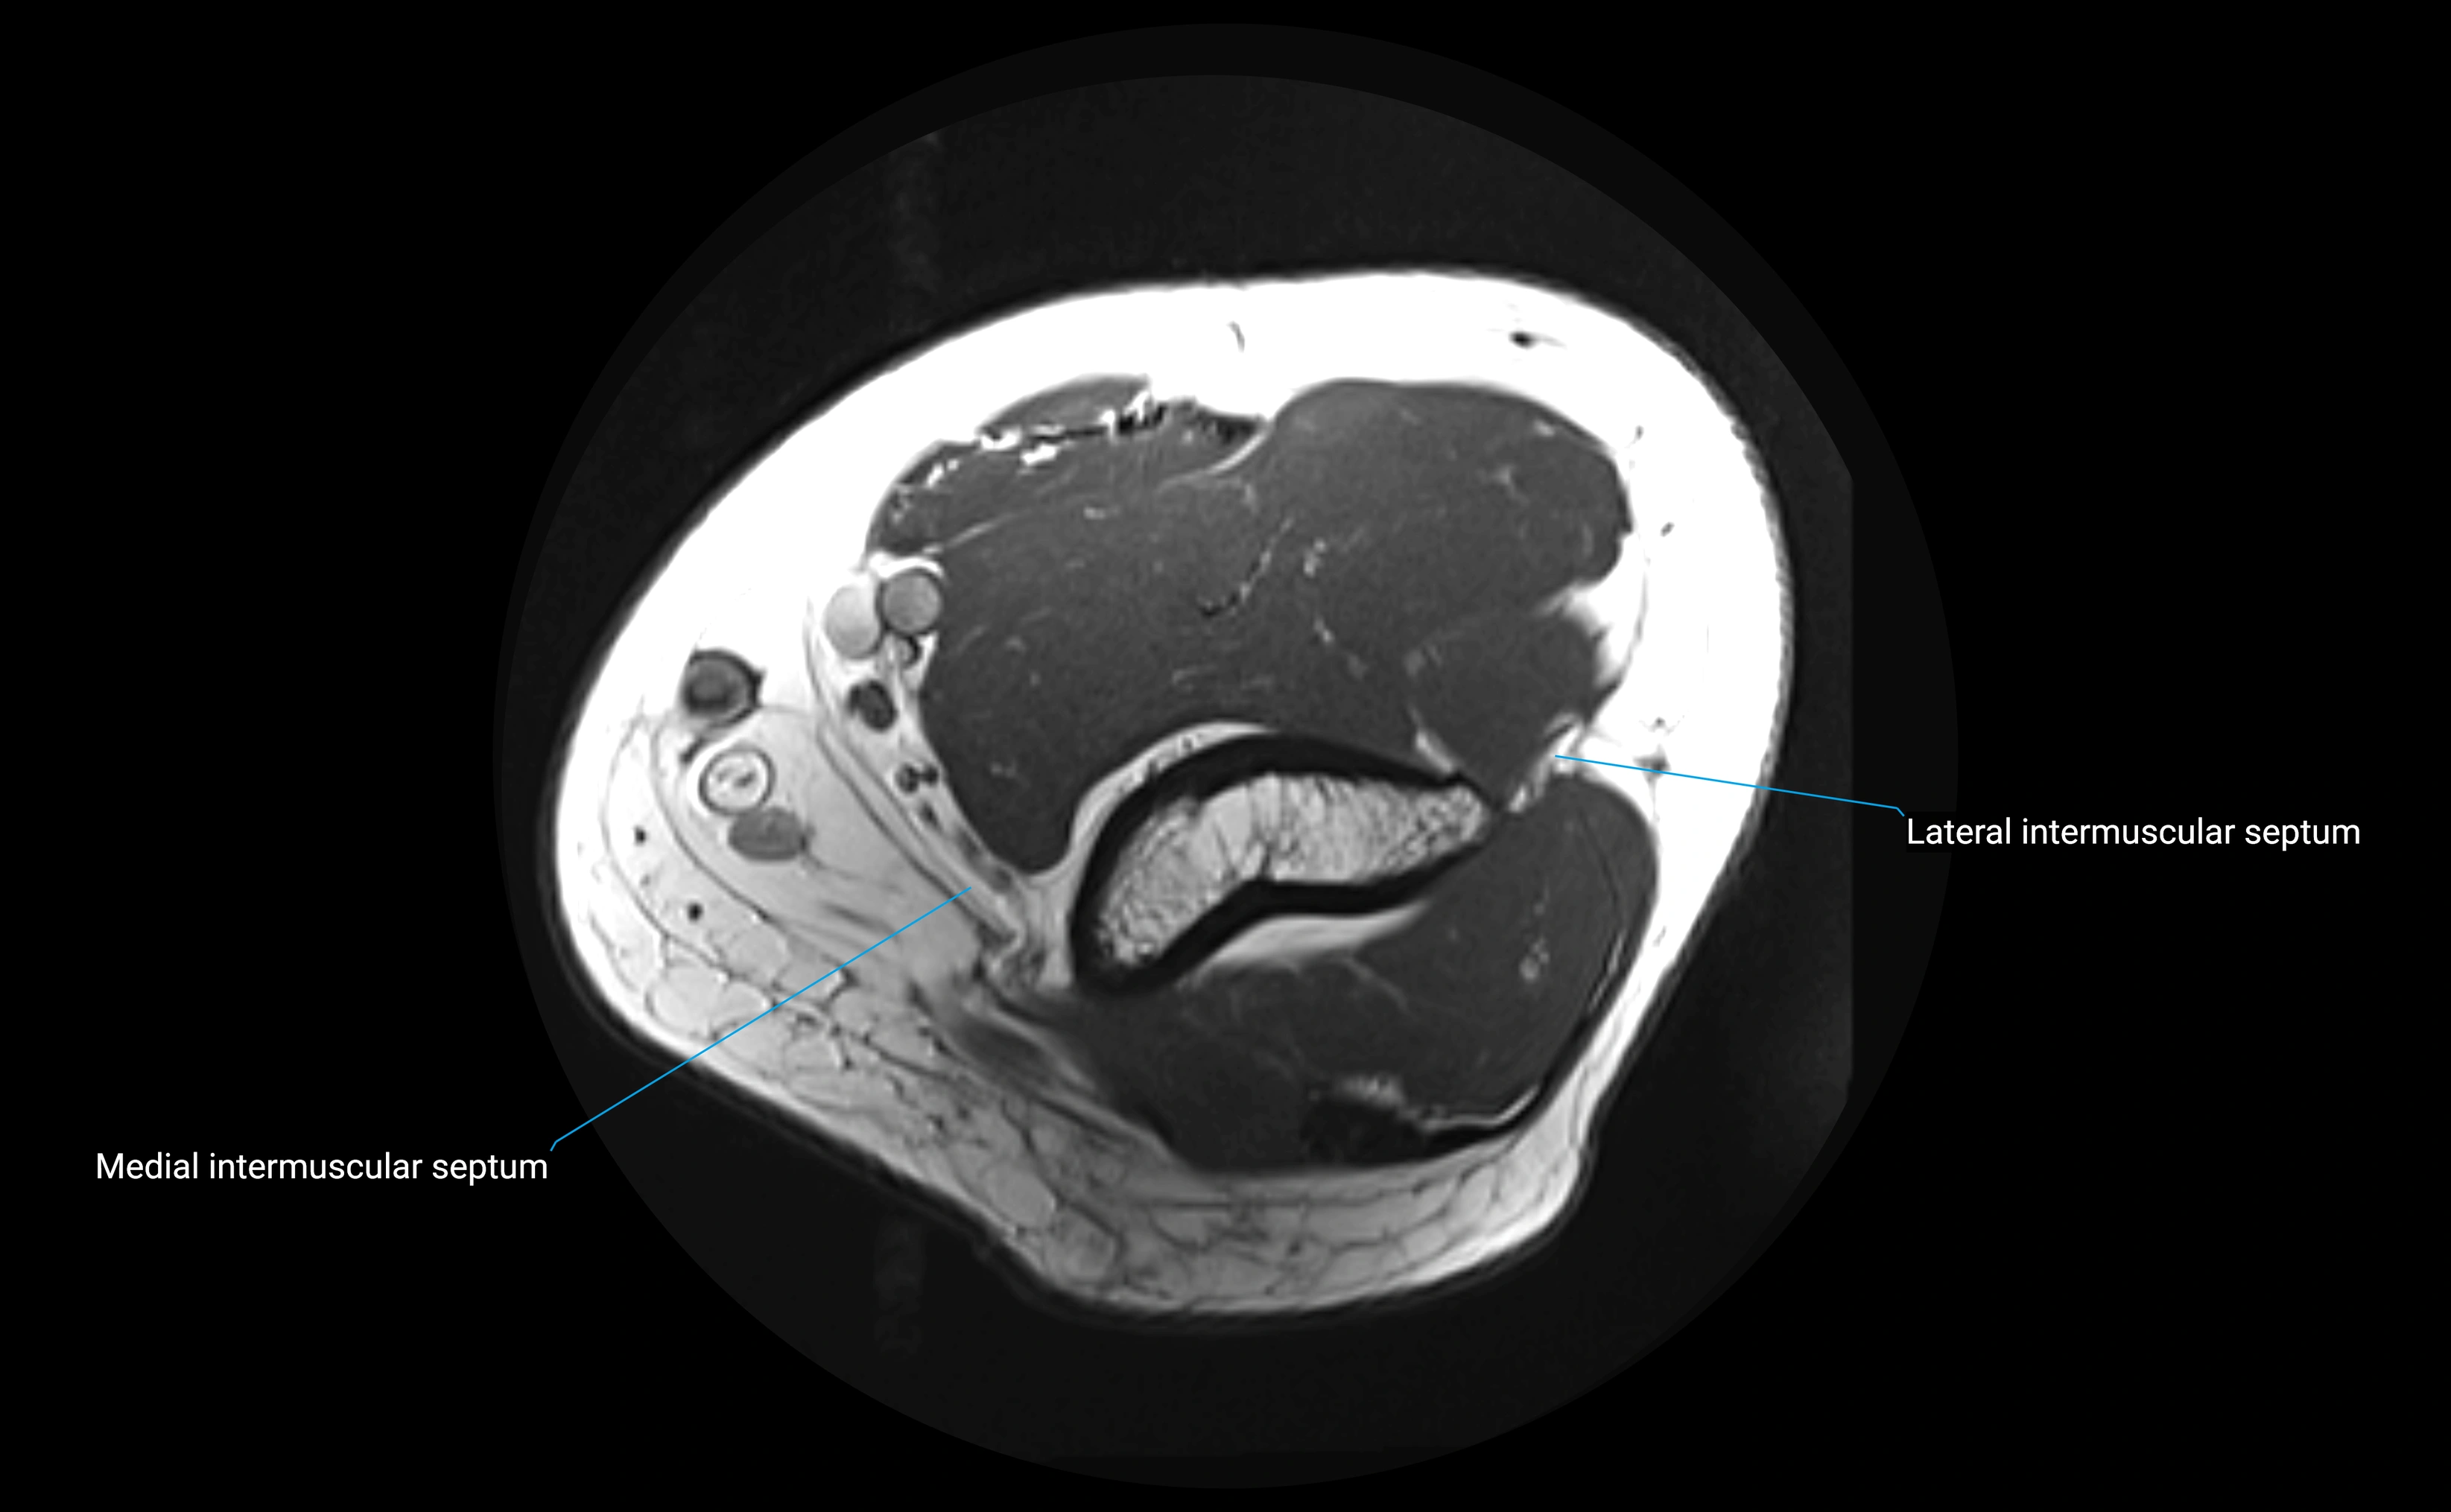

MRI images

image